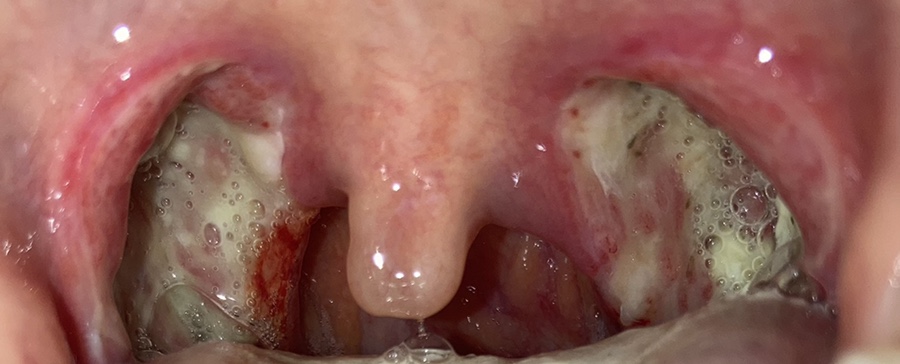

이건 수술 후 사진을 찍은 거야.

목젖이 부어 보이지 않을 정도다. 혀 뒤에 있다; 잠을 못 자고 옆으로 자야 한다. 바른 자세로 자면 숨을 쉴 수 없어 ㅋㅋㅋ 1층 내려서 의사를 만나고 목도 봐주고 출혈 등 주의사항을 말해줬고 병실에서는 약도 가루약으로 많이 받아 12시쯤 퇴원했다.

목젖은 가라앉았지만 전기로 부서졌다는데 사흘째가 되자 딱지가 심해졌다. 사진은 셋째 날과 넷째 날이 같았기 때문에 넷째 날은 찍지 않았다.

5일째가 되자 딱지가 붙었다. 목젖도 아직 부은 것 같아. 그리고 목이 너무 아파 아직 옆으로 자야해. 그리고 목이 부어서 그런지 내가 잘 때 “이~~~~~~~~~~~~~~~~~~~~~~~~~~~~~~~~~~~~~~~~~~ 인터넷을 검색해보니 수면장애였다. 목이 이렇게 부어 있는데 안 날 리가 있나 보군.

점점 벗겨지는 게 보여. 그래도 여전히 아프다. 아플 때만 먹으라는 약 하루에 세 번은 꼭 먹게 됐다. 먹지 않으면 아픔을 참을 수 없어.아플 때만 먹으라는 약이 앞면에는 T/A, 뒷면에는 JANSSEN이라고 적혀 있는데 인터넷에서 검색해보면 이름은 울트라셋 정으로 중등도-중증의 급, 만성통증 때 먹는 약이다. 부작용이 과다 복용하면 속쓰림이었는데 제가 이것도 모르고 4개 먹고 토할 것 같아 힘들었던 적이 두 번 있었다. 두 번째가 되고 나서 벌써 세 개 이상은 먹지 않았다.

점점 피부가 보이기 시작한다.하지만 역시 아픔은 가시지 않는다.